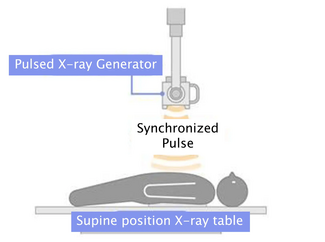

The procedure was performed under general anesthesia with three-dimensional TEE guidance, and periprocedural prophylactic antibiotics were given. The anterior mitral leaflet perforation measured 6 x 8 mm (area, 0.37 cm2), and the anterior mitral leaflet length was measured at 22 mm. As the left atrial (left ventricular, for this case) disc for a 5 mm Amplatzer septal occluder (St. Jude Medical) was 17 mm, it was felt that the device would not restrict the motion of the leaflet and still adequately seal the perforation.

The procedure was performed under general anesthesia with three-dimensional TEE guidance, and periprocedural prophylactic antibiotics were given. The anterior mitral leaflet perforation measured 6 x 8 mm (area, 0.37 cm2), and the anterior mitral leaflet length was measured at 22 mm. As the left atrial (left ventricular, for this case) disc for a 5 mm Amplatzer septal occluder (St. Jude Medical) was 17 mm, it was felt that the device would not restrict the motion of the leaflet and still adequately seal the perforation.

Initially, right heart catheterization was performed that demonstrated pulmonary arterial pressure of 40/20 with mean pulmonary capillary wedge pressure of 18 mm Hg and V waves up to 22 mm Hg. Simultaneously, left heart catheterization revealed LV end diastolic pressure of 17 mm Hg, ruling out mitral stenosis. A BRK needle (St. Jude Medical) was used to perform transseptal puncture under echocardiographic guidance and a Mullins transseptal sheath (Medtronic Inc.) was advanced through the interatrial septum in a superior location within the fossa ovalis. Intravenous heparin was given at this point. Mean left atrial pressure was recorded at 18 mm Hg with prominent V waves up to 40 mm Hg. The Mullins sheath was then removed and a medium curl Agilis NxT catheter (11.5 Fr outer diameter, 8.5 Fr inner diameter, St. Jude Medical) was advanced into the left atrium and directed toward the base of the anterior mitral leaflet. Through the Agilis catheter, an 8 Fr EBU 3.75 guiding catheter (Medtronic Inc.) was then advanced to its tip. Another multipurpose catheter was then nested through the guiding catheter using a triple telescoping “mother and child” approach. An exchange-length 0.035˝ angled Glidewire (Terumo Medical Corporation) was then advanced through the leaflet perforation using three-dimensional TEE guidance in an antegrade fashion. Over the Glidewire, the multipurpose catheter was passed through the defect into the LV apex. The Glidewire was then exchanged for an Amplatz Superstiff wire (Boston Scientific), over which the EBU guiding catheter was advanced in the LV cavity (Figure 2). Once the guiding catheter was appropriately positioned in the LV midcavity, the multipurpose catheter as well as the stiff wire were removed. Then, a 5 mm Amplatzer atrial septal occluder was loaded into the guiding catheter and deployed successfully to the anterior mitral leaflet perforation under TEE guidance (Figure 3). On color Doppler, there was no residual MR through the leaflet perforation and only 1+ functional (central) MR with excellent device stability (Figures 1 and 4). The anterior mitral leaflet had preserved mobility and there was no obstruction of the LVOT (Figure 4). Mean left atrial pressure after the repair was 15 mm Hg with diminished V waves. Final transmitral gradient was 4 mm Hg with mitral valve area of 2.5 cm2. Procedural fluoroscopy time was 27 minutes. The postprocedure course was uneventful and the patient was discharged on aspirin and clopidogrel on postprocedure day 1. At 1-month follow-up, he was in New York Heart Association functional class I. He developed transient mild hemolytic anemia, which did not require transfusion. On follow-up echocardiogram, there was no residual MR through the defect and only 1+ central MR.

Initially, right heart catheterization was performed that demonstrated pulmonary arterial pressure of 40/20 with mean pulmonary capillary wedge pressure of 18 mm Hg and V waves up to 22 mm Hg. Simultaneously, left heart catheterization revealed LV end diastolic pressure of 17 mm Hg, ruling out mitral stenosis. A BRK needle (St. Jude Medical) was used to perform transseptal puncture under echocardiographic guidance and a Mullins transseptal sheath (Medtronic Inc.) was advanced through the interatrial septum in a superior location within the fossa ovalis. Intravenous heparin was given at this point. Mean left atrial pressure was recorded at 18 mm Hg with prominent V waves up to 40 mm Hg. The Mullins sheath was then removed and a medium curl Agilis NxT catheter (11.5 Fr outer diameter, 8.5 Fr inner diameter, St. Jude Medical) was advanced into the left atrium and directed toward the base of the anterior mitral leaflet. Through the Agilis catheter, an 8 Fr EBU 3.75 guiding catheter (Medtronic Inc.) was then advanced to its tip. Another multipurpose catheter was then nested through the guiding catheter using a triple telescoping “mother and child” approach. An exchange-length 0.035˝ angled Glidewire (Terumo Medical Corporation) was then advanced through the leaflet perforation using three-dimensional TEE guidance in an antegrade fashion. Over the Glidewire, the multipurpose catheter was passed through the defect into the LV apex. The Glidewire was then exchanged for an Amplatz Superstiff wire (Boston Scientific), over which the EBU guiding catheter was advanced in the LV cavity (Figure 2). Once the guiding catheter was appropriately positioned in the LV midcavity, the multipurpose catheter as well as the stiff wire were removed. Then, a 5 mm Amplatzer atrial septal occluder was loaded into the guiding catheter and deployed successfully to the anterior mitral leaflet perforation under TEE guidance (Figure 3). On color Doppler, there was no residual MR through the leaflet perforation and only 1+ functional (central) MR with excellent device stability (Figures 1 and 4). The anterior mitral leaflet had preserved mobility and there was no obstruction of the LVOT (Figure 4). Mean left atrial pressure after the repair was 15 mm Hg with diminished V waves. Final transmitral gradient was 4 mm Hg with mitral valve area of 2.5 cm2. Procedural fluoroscopy time was 27 minutes. The postprocedure course was uneventful and the patient was discharged on aspirin and clopidogrel on postprocedure day 1. At 1-month follow-up, he was in New York Heart Association functional class I. He developed transient mild hemolytic anemia, which did not require transfusion. On follow-up echocardiogram, there was no residual MR through the defect and only 1+ central MR.

For percutaneous leaflet repair, high-quality two-and three-dimensional TEE are essential to delineate defect dimensions and motion of the anterior mitral leaflet in relation to the left ventricular outflow tract (LVOT). We utilized real-time three-dimensional TEE of the mitral valve as well as fluoroscopy to direct the guiding catheter and deploy the device. A triple-telescoping catheter technique that has been previously described was used to cross the very medial and somewhat posterior defect.20 For device selection, it is important to consider the diameters of the waist and two retention discs. We chose an Amplatzer septal occluder due to the very low profile and small disc diameters, which minimized the potential of restricting leaflet motion or obstructing the LVOT. Although use of an Amplatzer vascular plug has been described for a mitral leaflet perforation as a complication of mechanical aortic valve replacement, this device has substantial height and may not be the ideal choice for patching a leaflet perforation.7